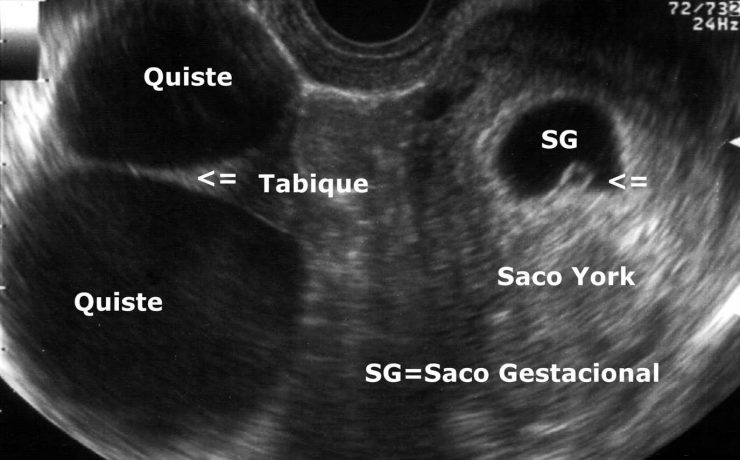

El desarrollo embrionario y fetal del riñón y de las vías urinarias es un proceso biológico extraordinariamente complejo. La formación del riñón definitivo se inicia a partir de la quinta semana de vida intrauterina y su desarrollo depende de la interacción de sus dos compartimientos tisulares; la yema ureteral que